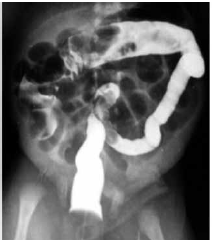

Raio-X de abdome com distensão gasosa difusa em intestino delgado. Enema opaco com contraste hidrossolúvel, conforme imagem a seguir:

Após a realização do enema opaco, houve eliminação de grande quantidade de mecônio, com melhora da distensão abdominal. Não houve novos episódios de vômitos, e o paciente apresentou boa aceitação de dieta e evacuações diárias. Atualmente, com vinte dias de vida, o paciente mostra-se assintomático.